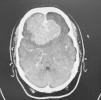

Caso clínicoAnalizamos las alteraciones de conducta causadas por un meningioma orbitofrontal en una mujer de 36 años. Las características clínicas y psicológicas del cuadro son reflejadas.

Case reportWe analyzed the behavioral disturbances caused by an orbitofrontal meningioma in a 36-years-old female. The clinical and psychological features are appointed.